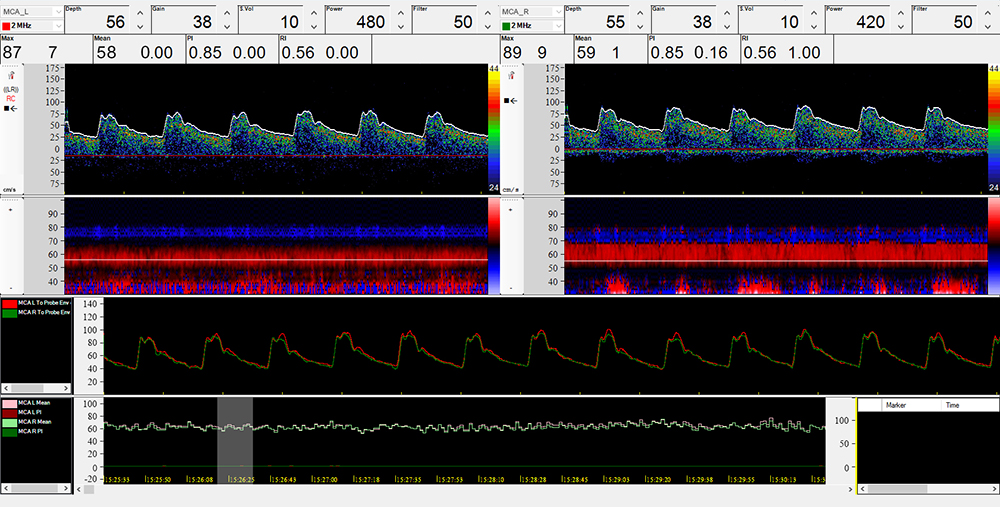

Transcranial monitoring is a helpful extension in Doppler Sonography. This method allows the recording of the flow velocity, of changes in the flow velocity, and also of the characteristic profile of the intrinsic curve (pulsatility) over a longer period. It can thus provide the user with valuable information.

This answers the desire for a non-invasive, continuous recording method to measure cerebral blood flow during pre-operative, peri-operative, and post-operative measures. Hence the possibilities for diagnostics can be significantly extended, and effects as reactions to medicinal and operational therapies can therefore be controlled and documented.

By means of optimised probe fixations, continuous bilateral long-term recordings, for example in the intensive care unit, during an operation, or in a stroke unit, can be conducted easily and without problems.

Constant industry advances and further developments as a result of evolving medical findings means monitoring today comprises additional valuable diagnosis tools, which go far beyond simple control monitoring: